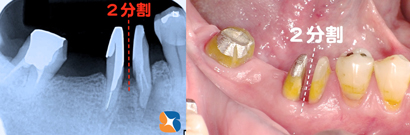

奥歯をメンテナンスしやすいように分割保存 奥歯を2つに分割して抜歯を回避しました。

ブリッジ 2分割したことで、今まで清掃が不可能であった股間部を、細い歯間ブラシで清掃可能となりました。装着して3年経ちますが、特に問題もなく、快適な食生活を送られているとのこと。